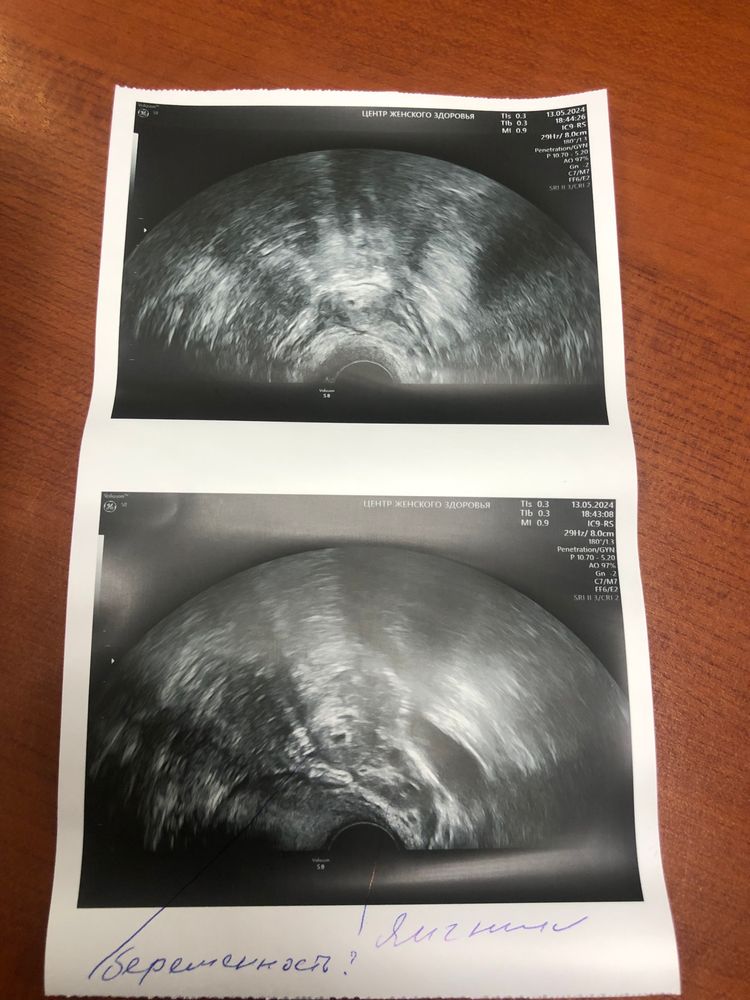

Внематочная в яичнике? Где желтое тело?

Анечка, о,вы тоже с Томска)) 9числа сдала ХГЧ был 1.033,а до этого 7 числа был 972. Маленький прирост. Где желтое тело,меня волнуе вопрос? Эндометрий растет🤔что за образование в яичнике?

Анечка, Изображение

Ирина , кажется беременность у вас в яичнике.. Судя, даже по надписи на самой фотографии.

Эльмира Богомягких, там под вопросом. Еще нужно перепроверять.